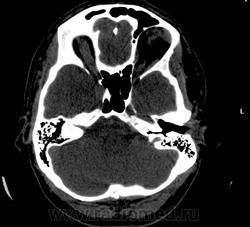

Прошу разрешить спор. По КТ - норма. Женщина, 1967г.р., жалобы на головную боль, больше в затылочной области. По-моему, не КТ-шное это дело но всеж...

Открыл. В мозгу ничего осбенного не увидел. По поводу Киари ничего не скажу, на аксиалах не вижу, а реконструкции эти срезы не строят Да и отношусь я к этой патологиии как к норме.

Но мне показалось, что всеж, для 1967г.р., не очень норма, придираюсь уже, пора на покой .

Аномалию Арнольда-Киари 1типа.

На МРТ выставили  аномалию Арнольда-Киари 1, нам сказали фу... На что я ответил, что по " ловцу и рыба". Во - первых, линию на КТ провести сложно ( в данном иссл.), во-вторых - естественные артефакты костей основания. И вообще пошли на...МРТ! Но осадок остался.

Для Арнольда-Киари I МРТ - как раз и есть метод диагностики, а на КТ это дело можно лишь заподозрить. Плюньте на осадок. Ну хотите, я плюну?) Тока отойдите, а то разъест))).